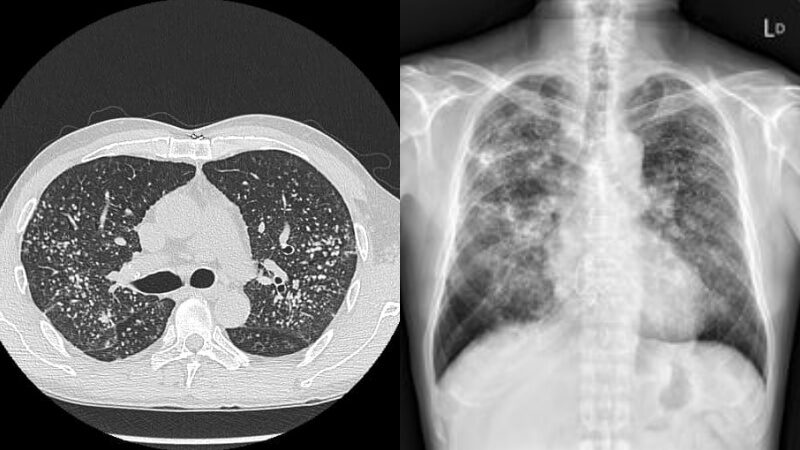

นพ. ซู อี้เฟิงเปิดเผยว่า ผู้ป่วยชายคนนี้ไม่สูบบุหรี่เลย แต่จู่ ๆ เขาหายใจไม่ออก ป่วยเป็นโรคหอบหืดมาหลายเดือนจึงตัดสินใจไปโรงพยาบาลแผนกทรวงอกเพื่อรับการรักษา แพทย์พบนิ้วของเขาเริ่มเป็นภาวะนิ้วตะบองอย่างเห็นได้ชัด จึงแนะนำให้ทำการตรวจด้วยรังสีเอกซ์

ซึ่งแพทย์พบว่าก้อนเนื้อในปอดหลายพันก้อนทำให้ผู้ที่เป็นโรคทริปโปโฟเบียมึนงงที่หนังศีรษะ พร้อมทั้งเตือนด้วยว่า "ถ้าคุณเห็นนิ้วของคุณกลายเป็นกระบอง อย่าลืมไปพบแพทย์เพื่อตรวจสุขภาพ"